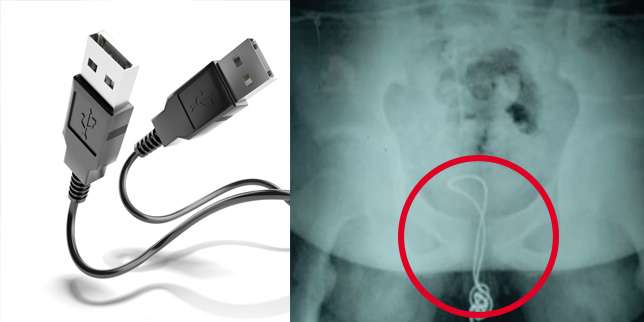

Menurut Dokter Xu Liyan yang bekerja di RSA Harbin mengatakan remaja itu memotong salah satu ujung kabel USB dan memasukkannya melalui uretra-nya.

" Kabel itu mencapai kandung kemihnya. Namun kabel itu kusut hingga membuatnya tersangkut. Akibatnya kabel itu tidak bisa dikeluarkan," jelas Dokter Liyan.

Dokter Liyan tidak punya pilihan lain selain mengeluarkan kabel USB yang tersangkut itu dengan cara operasi.

Saat ditanya kenapa melakukan hal konyol itu, bocah itu mengaku penasaran tentang alat kelaminnya.

Dia akhirnya diperbolehkan pulang dari rumah sakit setelah dua minggu menjalani pemulihan.